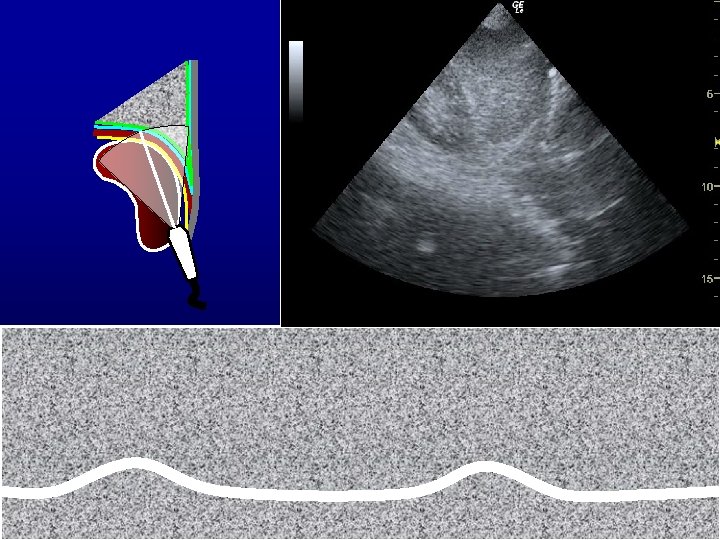

DIAFRAMMA • Scansioni trans-epatiche e trans-spleniche per visualizzare la cupola diaframmatica – a dx per via sottocostale tra l’emiclaveare e l’ascellare anteriore – a sn per via intercostale tra l’ascellare anteriore e l’ascellare media • Orientamento della linea M-mode ortogonale rispetto alla cupola diaframmatica • Valutazione dell’escursione diaframmatica cranio-caudale • Valori normali (mm) M F – inspirazione tranquilla – ispirazione massimale 18 ± 4 70 ± 10 16 ± 4 60 ± 10

ECO SEPSI RESPIRAZIONE LA FUNZIONE B • Il grado di impegno parenchimale polmonare (interstiziale e da consolidamento) correla inversamente con la prognosi e con la possibilità di recupero dell’autonomia nella ventilazione • Anche la funzione diaframmatica in respiro spontaneo (valutabile con il movimento caudale delle cupole o con l’ispessimento del muscolo) può essere predittiva della possibilità di recupero dell’automomia ventilatoria • Il grado di impegno parenchimale fornisce anche una stima del postcarico dx e permette di valutare preventivamente la tolleranza al carico volemico

ECOMONITOR RESPIRAZIONE B • La monitorizzazione ecografica del grado di impegno parenchimale polmonare e della funzione diaframmatica consente di prevedere la necessità di supporto ventilatorio e l’evoluzione clinica • Anche la funzione diaframmatica può essere valutata ripetutamente durante fasi di respiro spontaneo per stimare la probabilitò di recupero dell’automomia ventilatoria